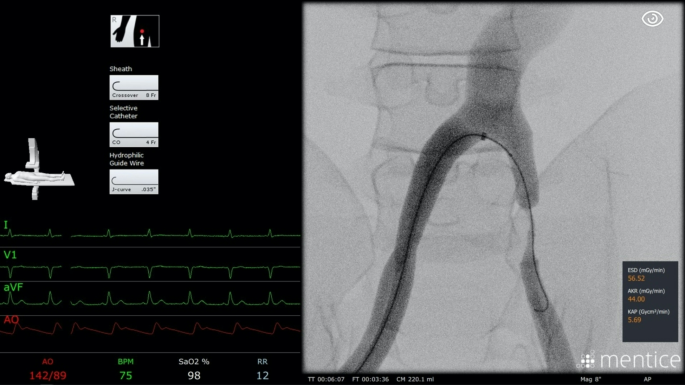

Exercises were conducted on the same endovascular simulator (VIST G5 Mentice, Gothenburg, Sweden) by using Microsoft Windows (Version 10.0.19045) at the Endolab Benjamin Franklin Campus Charité. This advanced simulator, equipped with a 3D monitor, control joysticks, fluoroscopy and CINE pedals, and a device insertion model, emulates a catheter lab environment as shown in Figs. 2 and 3. Participants engaged in VIST Exercise ID 212 by Mentice (VIST Case file: gen_ii_a212_mainconfig.xml), a peripheral arterial occlusive disease scenario (in the Iliac and SFA Intervention 1.4.0 Module), involving the treatment of iliac and superficial femoral artery lesions. Preset instruments were.

Experimental setup for the simulator training sessions, including the VIST G5 Mentice endovascular simulator, control joysticks, 3D monitor, fluoroscopy, CINE pedals, and device insertion model. This figure illustrates the comprehensive simulation environment used to emulate a catheter lab, enhancing the training experience for the participants.

The procedure started by introducing the sheath, selective catheter, and hydrophilic guidewire into the right femoral artery, through an existing opening in the simulator. The right femoral and iliac arteries, as well as the aortic bifurcation, were passed before reaching the first stenosis in the left iliac artery as shown in Fig. 4. The selective catheter was replaced by a balloon for a dilatation, and contrast medium was used to prove the dilatation. After exchanging back to the catheter, the left iliac common femoral and superficial femoral artery were explored to reach the second stenosis. This was treated by a stent substituted for the catheter as well. The intervention was finished by checking the success of the treatment with contrast medium in the superficial femoral artery and removing all instruments. The participants were allowed to use the amount of contrast medium and virtual fluoroscopy they needed to conclude the case successfully.

Screenshot of the simulator user interface during the treatment of a common iliac artery stenosis. The image shows the detailed interface with selected devices in the top left corner, highlighting the realistic and interactive elements of the simulation that aid in the training of angiographic procedures. The detailed and interactive interface helps participants familiarize themselves with actual procedural elements, leading to better preparation for real-world clinical scenarios.